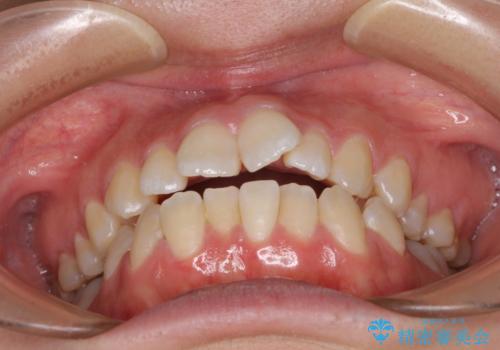

【モニター】オープンバイトをインビザラインで矯正治療

- 前歯の上下スペースによる食べにくさを気にして来院された患者様です。

インビザラインにより上下の前歯の隙間を閉じていくこととしました。

前歯のデコボコの解消と並行して上下の奥歯を圧下させるようにすることで、前歯を接触させるように計画しました。

上下の隙間に舌が入り込むことがオープンバイトの原因であったため、舌の筋肉のトレーニングも並行して行い、後戻りの抑制を図りました。